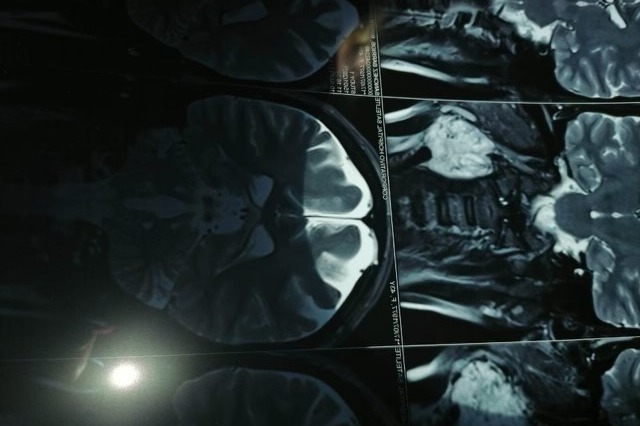

Hi, my name is Emily Sanchez. My aunt in Mexico, Miriam Sanchez, had COVID-19 back in October 2020, but was rushed to the emergency room because she was struggling to breathe. She was very sick for about a month before she started to recover. Soon after, my aunt noticed a bump forming on her neck that began growing and becoming painful to touch. The doctors discovered a tumor in between the two arteries that supply oxygenated blood from the heart to the brain, which is why she was having a hard time fighting the coronavirus. In the next few months, my aunt will need surgery to remove the growing tumor, or it is likely that she will have a stroke from the blockage of her arteries, preventing blood from reaching her brain. However, the procedure costs 1 million Mexican pesos, or around $50,000 U.S. dollars. My family and I ask that you help us raise $40k for Miriam's procedure as soon as possible so that she can get her tumor surgically removed.